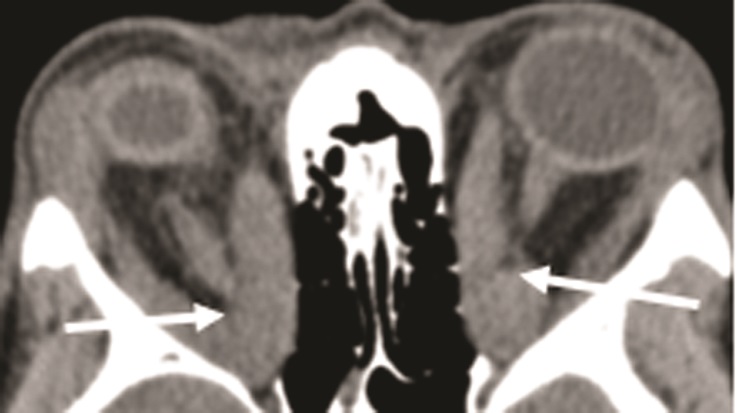

Основной характеристикой «миогенного» варианта является изолированное поражение ЭОМ, без увеличения в объеме РБК. У таких больных наблюдается нарушение функции ЭОМ с развитием диплопии, косоглазия, расстройством бинокулярного зрения, но без выраженного экзофтальма [11]. Фиброз развивается быстро, через 3–4 мес после первых клинических проявлений, что дополнительно ограничивает подвижность ЭОМ за счет образования спаек и развития контрактуры. У больных с миогенной формой практически отсутствует поражение роговицы. Эта форма ЭОП тяжело поддается лечению, а уже развившиеся диплопия и косоглазие не имеют обратного развития (рис. 5 на цв. вклейке, см. раздел Дополнительная информация). При исследовании рентгеновской плотности ЭОМ выявляются гиперденсные участки с повышением плотности (+50 — +98 HU).

Рис. 5. Клинические проявления ЭОП с избирательным вовлечением ЭОМ. Выраженная асимметрия положения глазных яблок в орбитах. б — МСКТ, корональная проекция OS — увеличение нижней прямой и наружной прямой мышц.